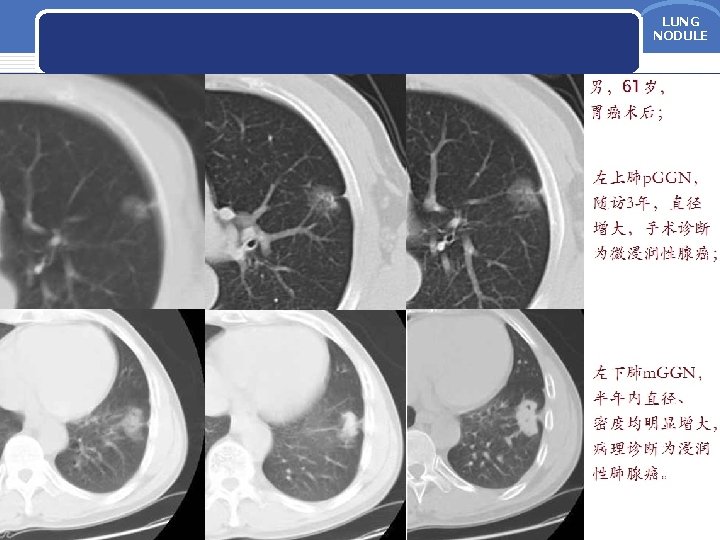

LUNG NODULE LUNG NODULE AAH p GGN 5